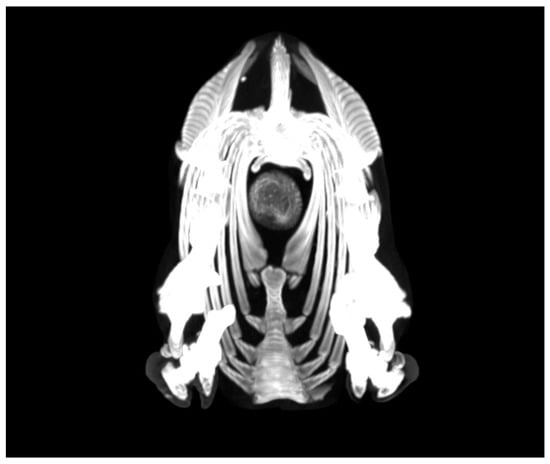

- Castells, E.; Lacasta, D.; Climent, M.; Pérez, M.; Sanromán, F.; Jiménez, C.; Ferrer, L.M. Diagnostic imaging techniques of the respiratory tract of sheep. Small Rumin. Res. 2019, 180, 112–126. [Google Scholar] [CrossRef]

- Ferrer, L.M.; Ramos, J.J.; Castells, E.; Ruíz, H.; Climent, M.; Lacasta, D. Use of Computed Tomography and Thermography for the Diagnosis of Respiratory Disorders in Adult Sheep. In Sheep Farming; IntechOpen: London, UK, 2020. [Google Scholar] [CrossRef]

- Grosso, F.V.; Tinkler, S.; Sola, M.; Miller, M.; Heng, H.G. Radiographic and computed tomographic appearance of caseous lymphadenitis in a goat. Vet. Radiol. Ultrasound. 2020, 61, E1–E6. [Google Scholar] [CrossRef]